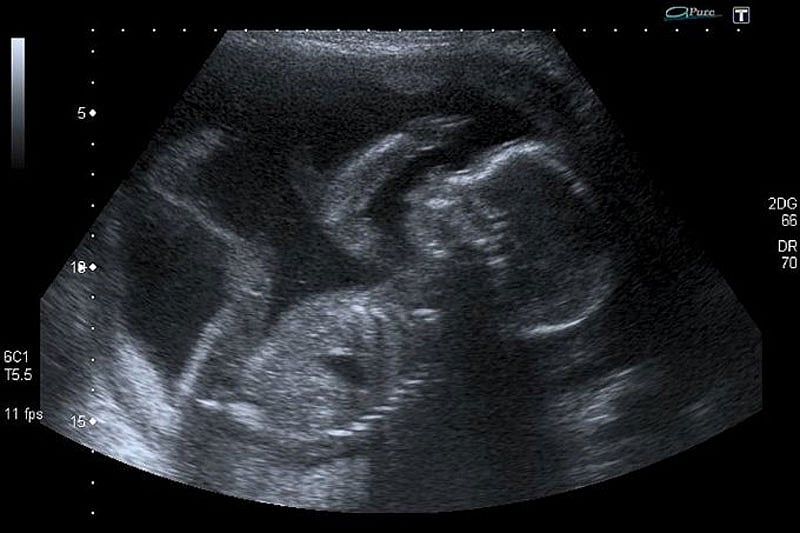

The girl, whose name and age are being withheld by federal officials, was about 22 weeks pregnant as of earlier this month. That would require an abortionist to dismember the fetus in the girl's womb.